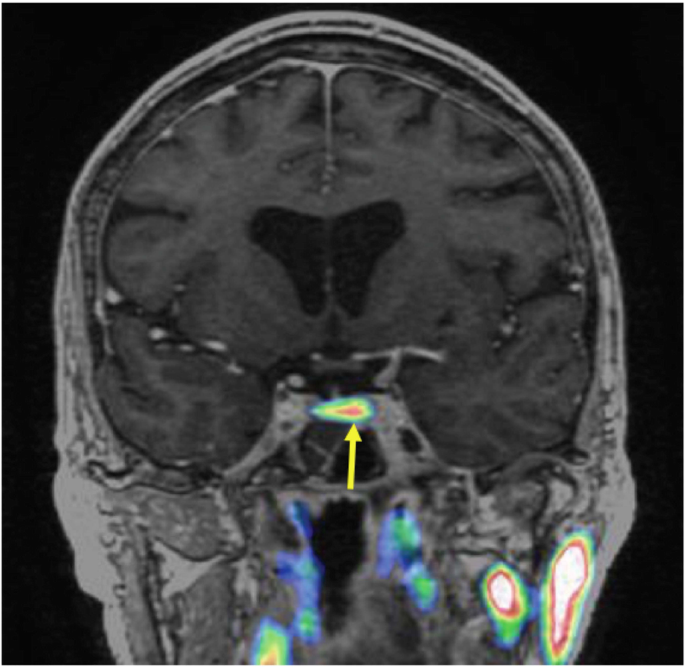

A pituitary MRI scan showed asymmetric enlargement of the gland, raising the possibility of a left-sided pituitary microadenoma (Fig. 2). An 11C-methionine PET/CT scan was performed and coregistered with a volumetric [fast spoiled gradient recall (FSPGR) MRI scan (Met-PET-MRICR)]. This demonstrated focal increased tracer uptake at the site of the suspected microadenoma (Figs. 3 and 4). Her biochemical and radiological findings were therefore consistent with the diagnosis of a TSH-secreting pituitary adenoma. The slightly raised IGF-1 and borderline suppression of GH on OGTT also raised the possibility of GH co-secretion. The patient was tried on a somatostatin analogue (SSA) first then a dopamine agonist but did not tolerate either (due to gastrointestinal side-effects). She declined pituitary surgery. She is currently managed with a beta-adrenergic blocker and is clinically euthyroid.

In recent years, functional pituitary imaging has been proposed as a useful tool for identifying the site(s) of a pituitary adenoma in patients with inconclusive MRI findings [26]. 11Carbon-methionine is an amino acid based PET tracer which, unlike the glucose-based tracer 18F-fluorodeoxyglucose, is preferentially taken up by normal pituitary tissue [27] with relatively low uptake by background brain tissue. Coregistration of 11C-Methionine PET/CT and volumetric (e.g FSPGR) MRI may be superior to MRI alone in localizing some pituitary microadenomas [16, 28, 29]

Inferior petrosal sinus sampling (IPSS) is often considered the gold standard investigation for the diagnosis of functional pituitary tumours. This is an invasive test that requires significant technical expertise. While more data is needed on the utility of Met-PET-MRICR there is some evidence to suggest it is a highly sensitive non-invasive test that could be considered as an alternative to IPSS [30]. In our case, although MRI raised suspicion of a left-side abnormality, no definite adenoma was seen. However, Met-PET-MRICR confirmed focal tracer uptake corresponding to this site.